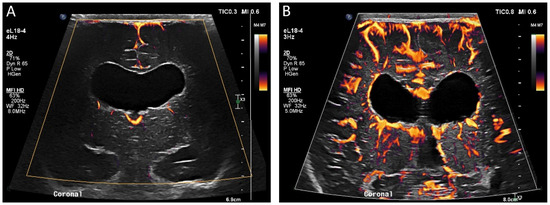

Figure 5.

(A) Ultrasound with color microvascular imaging in a 6 day old, former 32 week 2 day infant with multiple congenital anomalies including absence of the septum pellucidum. Overall reduced cortical and deep gray nuclei microvascular flow is observed. (B) Ultrasound with color microvascular imaging of a 51 day old, former term infant with congenital hydrocephalus. Overall increased microvascular perfusion is seen throughout the cortex, white matter, and deep gray matter compared to the infant in (A). The significance of these and similar findings has yet to be elucidated and may be of import for clinical management and prognostication.

Figure 6.

(A) Grayscale and (B) color microvascular imaging ultrasound a 13 day old, former 33 week 5 day infant with congenital heart disease and hypoxic respiratory failure on extracorporeal membrane oxygenation with seizures. Elevated flow is seen within the deep gray matter. This may reflect perfusion alterations in the setting of seizure, dysfunctional autoregulation, and/or evolving injury.